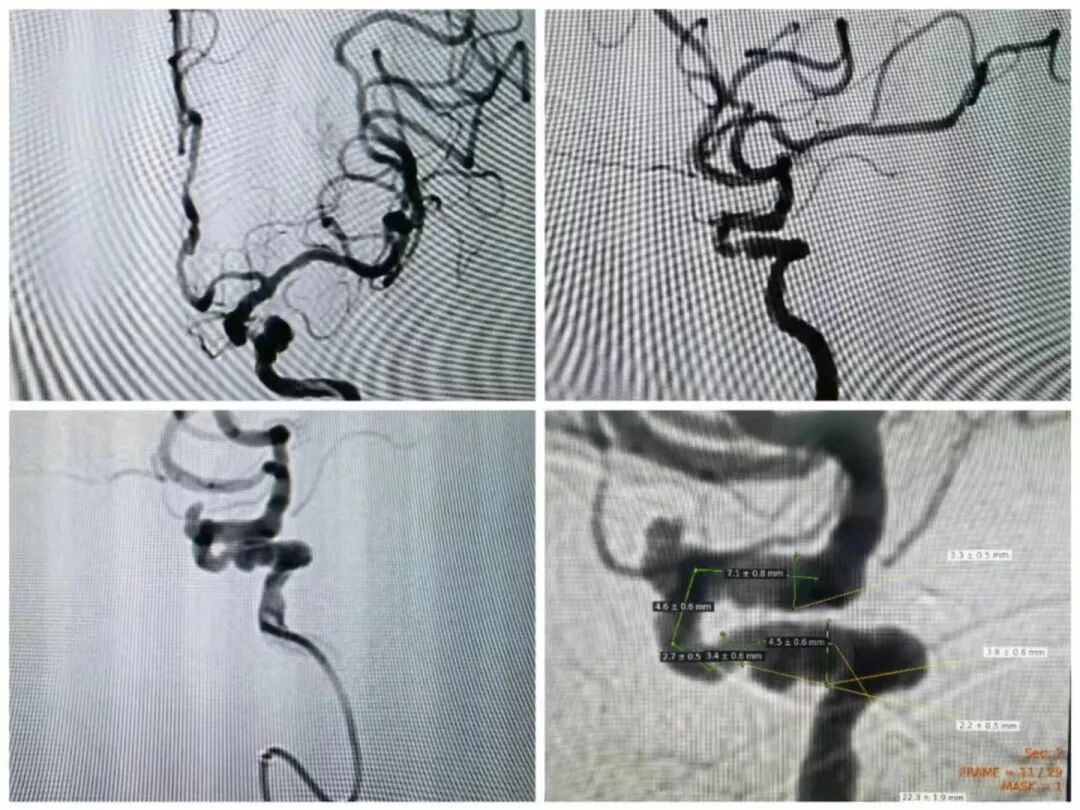

头颈部血管

DSA 技术在脑血管疾病以及颅脑的肿瘤等方面有着极大的诊断价值。主要用于检查颈动脉起始部,动脉起始部,颈内,颈外,椎动脉系统,基底动脉系统。其诊断的准确性、敏感性、科学性方面都很高。